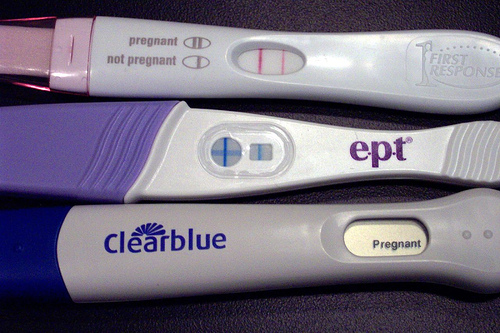

<a href="http://www.shutterstock.com/cat.mhtml?lang=en&search_source=search_form&version=llv1&anyorall=all&safesearch=1&searchterm=pregnant&search_group=#id=70529002&src=lkn4xJvTNaeOLnqN4TIRZg-1-74">pedrosala</a>/Shutterstock